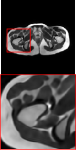

Figure 5 provides the qualitative comparison of the various methods on the four datasets at a scale of 4. The top, second, third, and bottom rows are the SR results under the FastMRI, clinical brain, clinical tumor and clinical pelvic datasets, respectively. The red boxes indicate the zoom-in region of complicated anatomical structures along with their corresponding error maps. Note that the brighter textures in the error maps, the lower the quality of the reconstructed images. As can be seen, compared to methods based on Transformers and CNNs, diffusion-based methods like DisC-Diff and DiffMSR (Ours) are capable of reconstructing high-realistic images with promising reconstruction metric scores (PSNR and SSIM). Nevertheless, while DisC-Diff can reconstruct high-precision MR images, it does not preserve the structure present in the original HR images, introducing some additional information that can affect medical diagnosis. In contrast, our method combines DM and PLWformer, which can preserve the original image’s structure while restoring high-frequency information.

In this section, we present more visual qualitative comparisons. Figures 8, 9, 10, and 11 show the reconstruction results of each method in FastMRI, clinical brain, clinical tumor, and clinical pelvic, respectively. As can be seen, although DisC-Diff can reconstruct MR images with high-frequency information, it fails to preserve the structure and content of the original Target HR image effectively, resulting in image distortion. In contrast, our proposed DiffMSR can restore high-frequency information while preserving the structure of the original HR image, indicating the effectiveness of the joint use of DM and PLWformer.